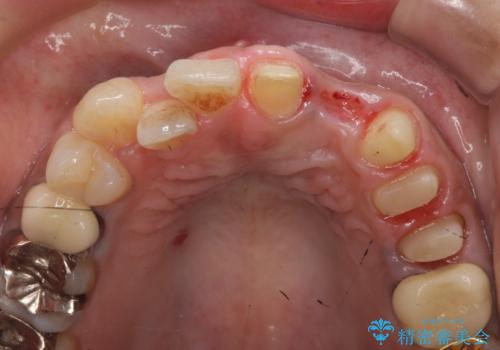

なお左上4に関しては縁下歯質を改善するため、歯冠挺出を行っております。

歯冠延長術について

歯冠長延長術とは歯肉弁根尖側移動術とも言い、歯の高さが低くクラウン(被せ物)による治療が難しい場合に、歯茎を歯根方向に下げることで歯の高さを確保する手術です。歯の高さが十分にあることで、外れにくいしっかりとしたクラウンを被せることができます。